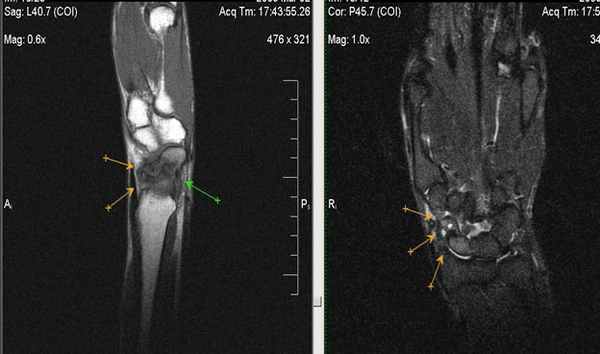

(Слева) МР-артрография в режиме Т1ВИ, коронарный срез: визуализируется крупный дефект ЛПС. Суставная щель расширена. Следует отметить наличиедегенеративных перфораций в центральной части ТФХК.

(Справа) МР-артрография в режиме Т2ВИ FS, коронарный срез: визуализируется крупный дефект ЛПС. Суставная щель расширена. Следует отметить неравномерное истончение хряща и кистозные изменения суставных поверхностей, обусловленные нестабильностью. Это говорит о том, что разрыв данной связки был биомеханически значим. (Слева) Артрография в заднепередней проекции: распространение контрастного препарата через дефект ЛПС в среднезапястный сустав. ПТС интактна.

(Справа) МР-артрография в режиме Т1ВИ, коронарный срез, этот же пациент: визуализируется интактный тыльный пучок ЛПС. Разрыв мембранозной порции на данном срезе не виден (располагается кпереди). Разрыв центральной мембранозной порции ЛПС часто протекает бессимптомно. (Слева) Непрямая МР-артрография в режиме Т1ВИ FS с КУ, коронарный срез: визуализируется значительное расширение ладьевидно-полулунного промежутка. Отмечаются признаки артрита лучеладьевидного сустава. Головчатая кость смещена проксимально в промежуток между ладьевидной и полулунной костями. Картина характерна для ПЛПК запястья.

(Справа) МР-артрография в режиме PD FS, сагиттальный срез, этот же пациент: определяется разрыв восстановленного фрагмента связки, имеющего аморфную структуру и неровный контур. Полулунная кость отклонена в тыльную сторону, что позволяет заподозрить ТНПС. Положение полулунной кости должно быть сопоставлено с осью ладьевидной кости на соседних срезах.